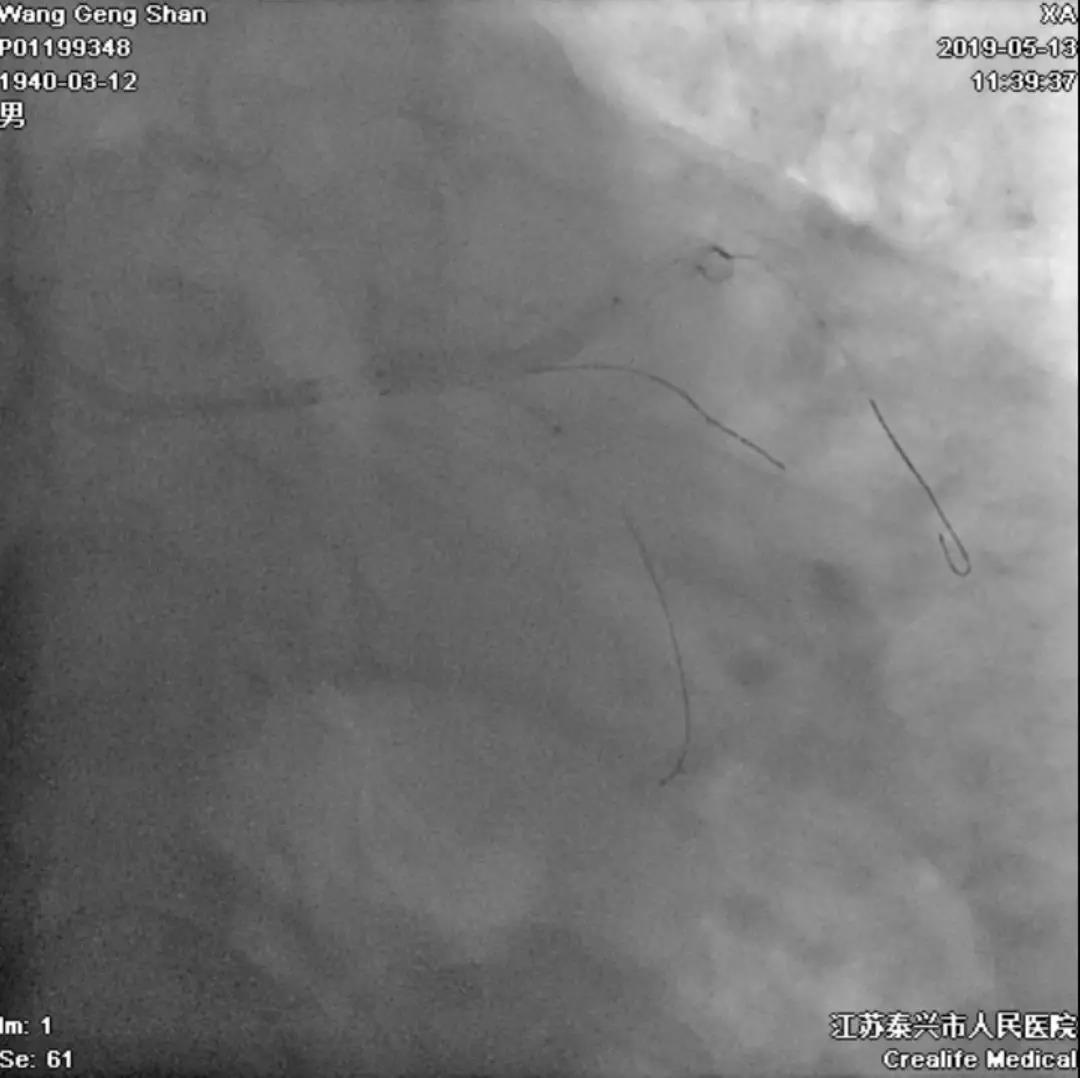

06 LM-LAD支架后扩张

交换回旋支导丝,非顺应性球囊顺序高压扩张

07 LM支架近段优化(POT)

左主干近段用大一号非顺应性球囊行高压扩张

IVUS评估,支架贴壁良好。